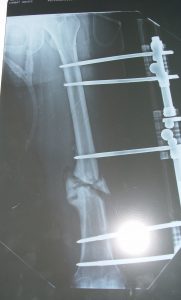

Humerus Psödoartrozlarının İlizarov

Yöntemi ile Tedavisi

1. Deformite ile birlikte Sert Psödoartroz

Bu tip psödoartrozlar genelikle yetersiz stabilite sonucu oluşmuşlardır. Patolojinin tedavisinde prensip, tedrici olarak deformitenin düzeltilmesi ve bir miktar distraksiyonla (monofokal distraksiyon osteogenezi) kallus oluşumunun stimülasyonudur. Deformite düzeltme prensiplerinden de bilindiği üzere eğer ekstremitede kısalık da mevcut ise menteşeler deformitenin konveks tarafında açı ortay üzerine yerleştirilmelidir. Psödoartroz hattı günde 0.5 mm distraksiyon yapacak şekilde ayarlanmalıdır. Çünkü klinik tecrübemiz sert psödoartrozlarda 1 mm / gün yapılacak bir distraksiyonun ağrıya sebep olacağıdır.

3. Defekt Psödoartrozlar

Genellikle birden çok kez cerrahi müdahele geçirmiş ya da osteomiyelitise bağlı kemik rezeksiyonu nedeniyle, çok nadiren de tümör rezeksiyonuna bağlı oluşmuş defektlerdir. Bilindiği gibi humerus da oluşan kısalık kimi otörlere göre 4cm bazılarına göre de 6 cm’ye kadar fonksiyonel bir yetersizlik ortaya çıkarmaz. Segment transportu monofokal osteogeneze göre daha komplike olduğundan 4-6 cm ‘lik defektler kadar psödoartroz mobil psödoartroz olarak kabul edilmelidir. Bunun üzerindeki defektlerde konvansiyonel olarak damarlı fibula grefti ya da allogreft uygulamalarının yanında, İlizarov’a göre segment transportu da bir tedavi seçeneğidir. Tümör rezeksiyonları dışındaki defektler genellikle 7 cm’nin altında olduğundan ( 4 cm kabul edilebilir defekt + 3 cm ilave kemik defekti) uygulanan teknik eksternal segment kaydırma olmalıdır. Bifokal osteogenezis olarak da isimlendirilen tedavinin süresini kısaltmak için önerilen bir yöntem de akut kısaltma ve tedrici uzatmadır. Aslında segment transporttan prensipte farklı olmayan bu uygulamada, hedef bölgenin kaynaması için geçen süre esnasında ekstremite uzatılacaktır.